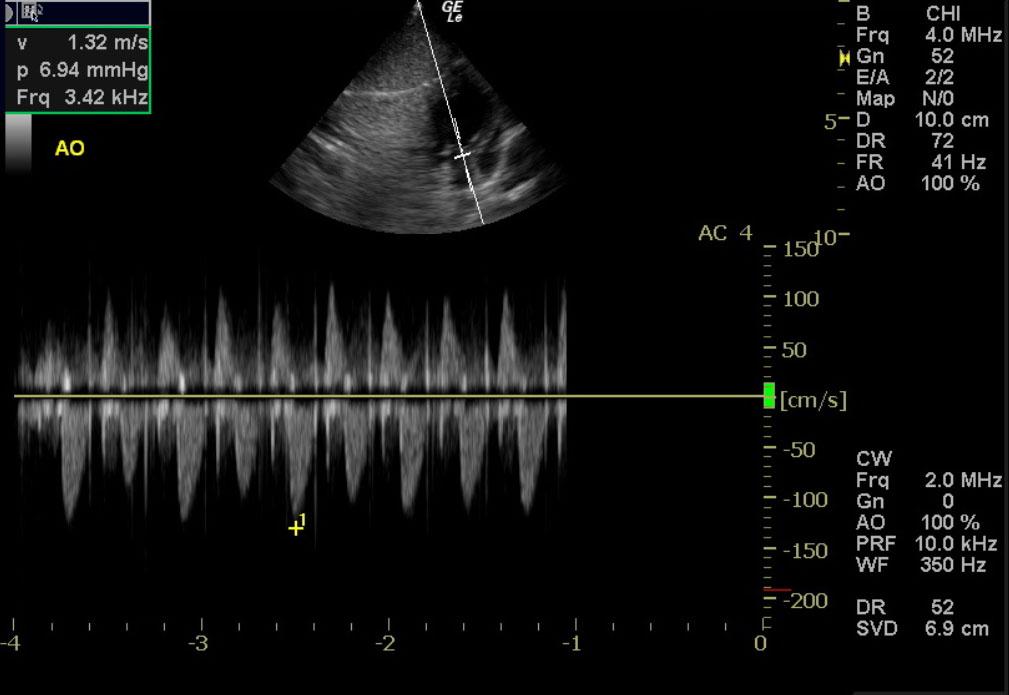

A one month old sheltie cross dog with a history of 5 of 7 littermates dying from parvovirus was presented for lethargy, and diarrhea. Parvovirus was identified in a littermate’s myocardium at necropsy.